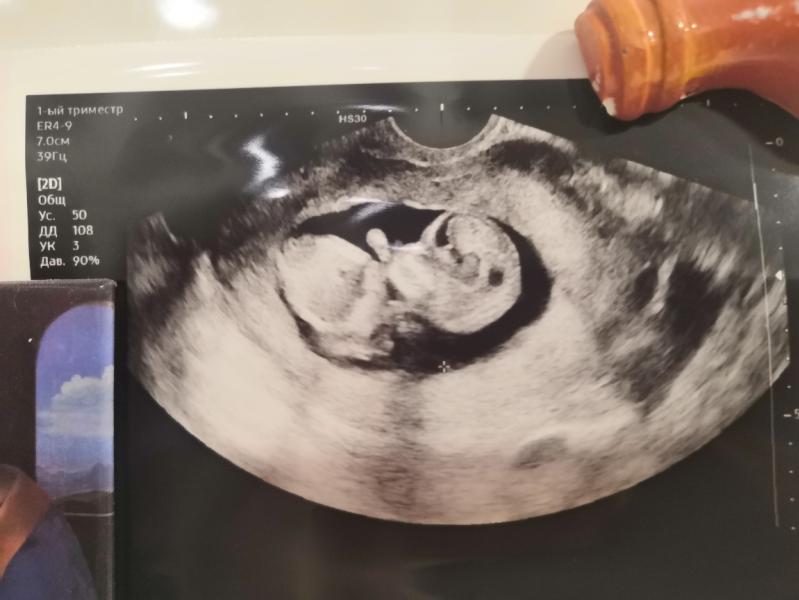

А внутри меня растёт жизнь и это самый лучший для меня подарок жизни❤️